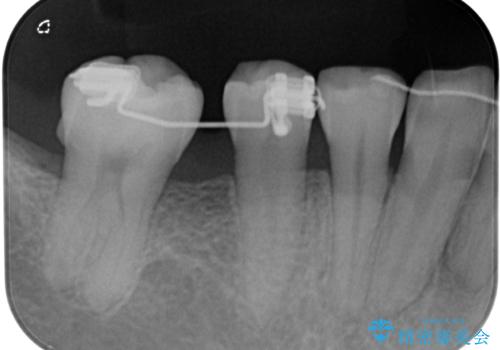

- 1本欠損したままの奥歯の治療を終えたいとのことで来院された患者様です。

奥歯が1本欠損した状態で矯正治療を行っていたそうですが、どのように治療を終了させるか未決のまま矯正装置を除去してしまい、暫く放置されている状態でした。

理想的には残っている歯のスペースを詰め、最後方にインプラントを埋入することが理想的ではありますが、矯正治療期間や費用の面から、前後に歯を大きくする補綴治療を行うことで対応することとなりました。